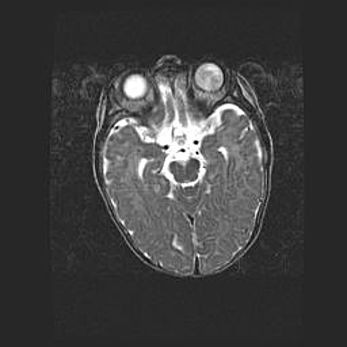

Неполная лизэнцефалия (пахигирия). Открытая гидроцефалия.

Возраст: 17 дней

Вес: 3110 г

Пол: мужской

Окружность головы: 33,5 см

Срок гестации: 35-36 недель

Лизэнцефалия—недоразвитие корковой пластинки и мозговых извилин в результате нарушения миграции нейронов коры. Поверхность мозговых полушарий гладкая. Микроскопически выявляется отсутствие нормальных слоев коры и скопление групп нейронов в подкорковом белом веществе.

Пахигирия—уменьшение числа вторичных извилин. В пораженном полушарии нервные клетки образуют толстый недифференцированный слой с неправильно расположенными нервными волокнами и группами гетеротопных клеток. Нервные клетки незрелые. Белое вещество истончено. При этом нередко аномально развит корково-спинномозговой путь.